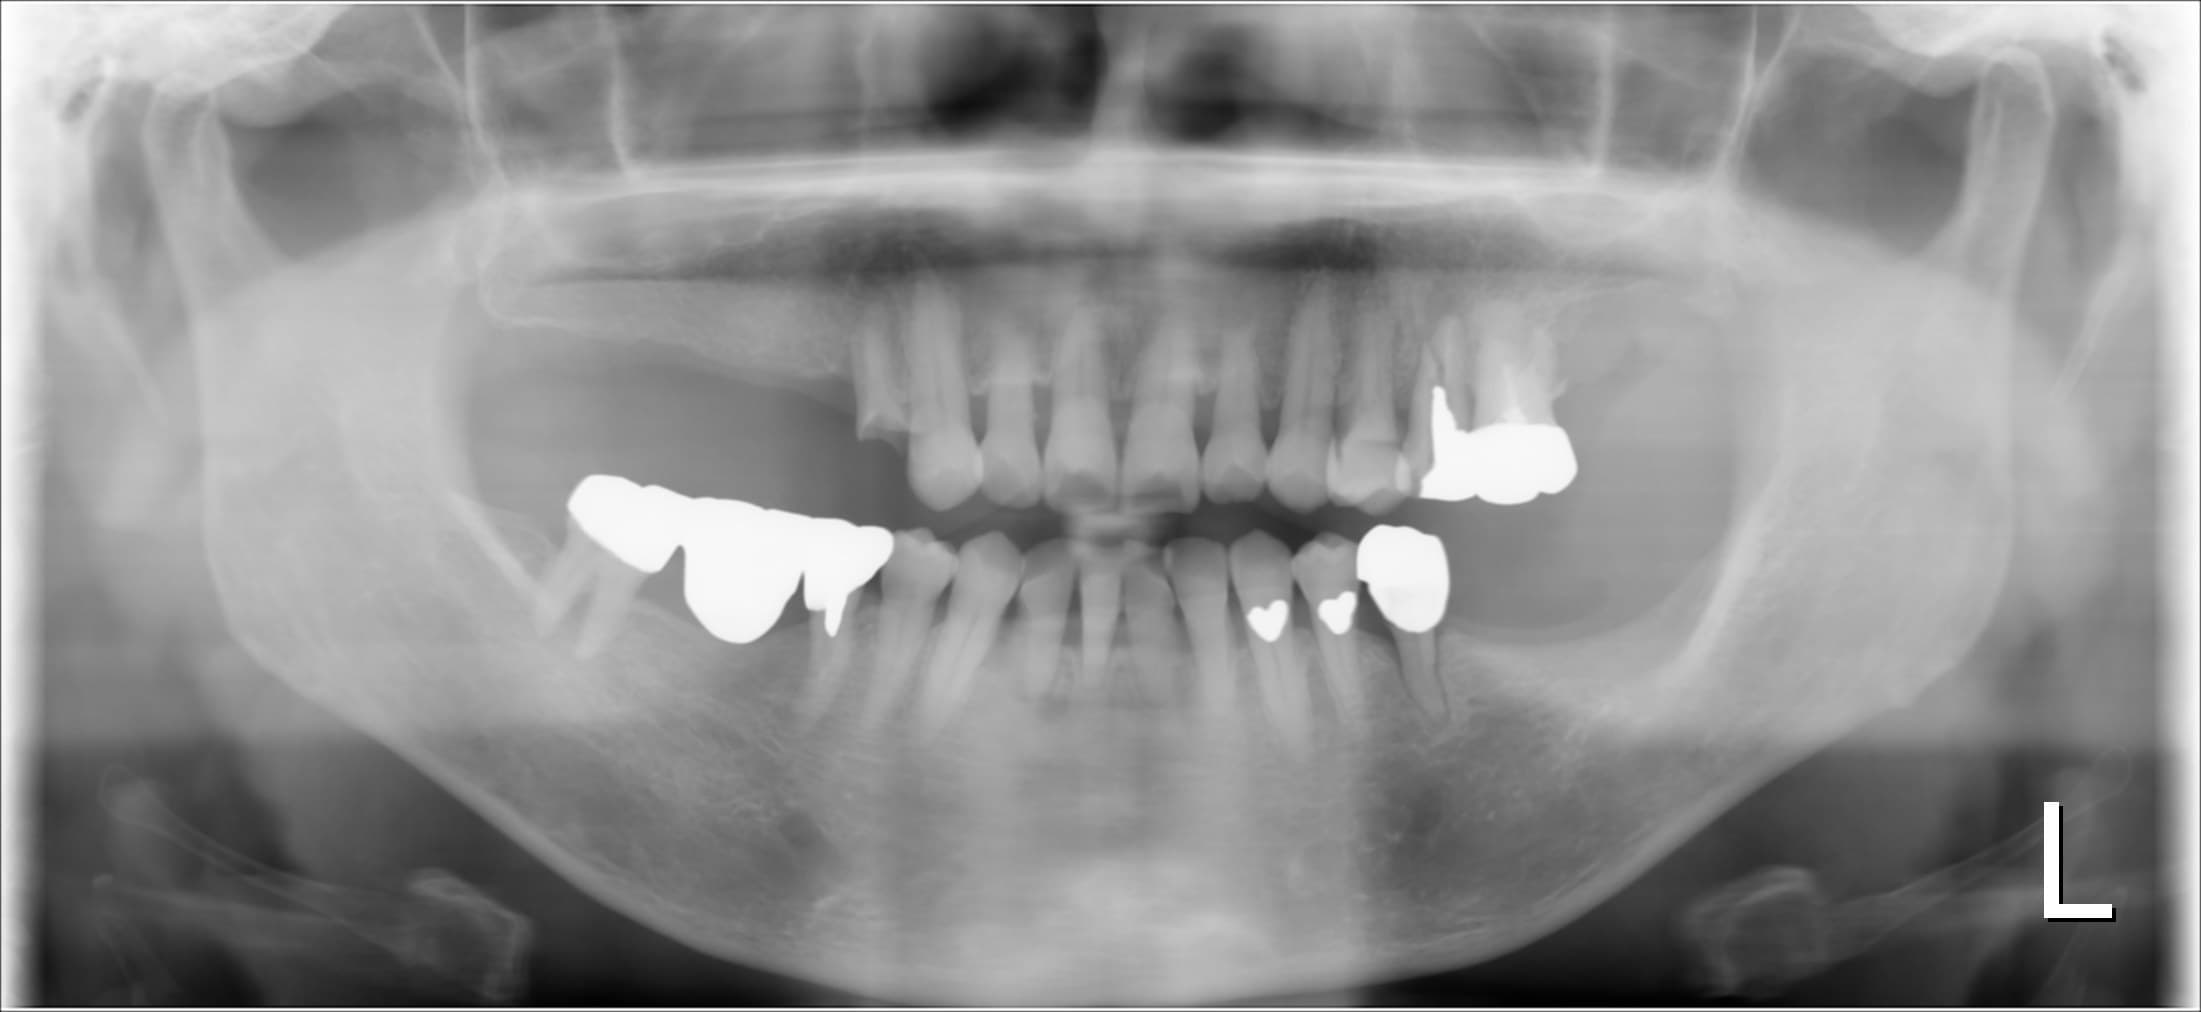

今回ご紹介する歯周専門治療のケースは、70代女性の方です。

最近奥歯が折れた事をきっかけに来院されました。

初診時

確かに、折れた歯や歯周病でグラグラする歯など、どうしようもない場合もありますが、事前に適切な予防や処置を行っていれば、最悪の事態を回避できるケースも少なくありません。

幸いにも、まだ前歯部は多く残っており今から予防の為の治療をすれば、現状の維持が可能であることをお伝えして、歯周専門治療を行うこととなりました。